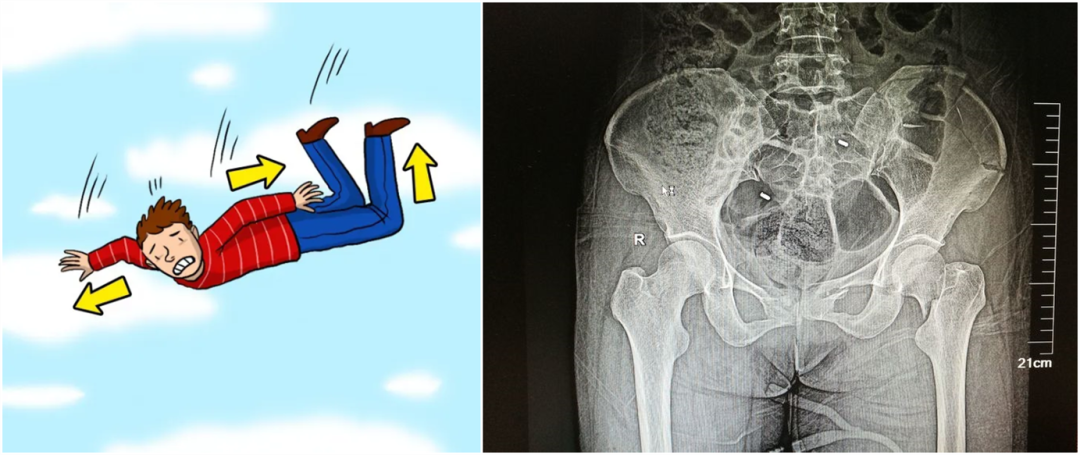

从暴力的大小来看,还可以细分为高能量的损伤和低能量的损伤。比如说,如果是车子撞的,从高处坠落,通常会造成高能量的损伤,而普通的跌倒造成的骨折,一般不太严重,可以说是低能量的损伤。

【医疗科普】:不稳定性骨折影像

不稳定性骨折